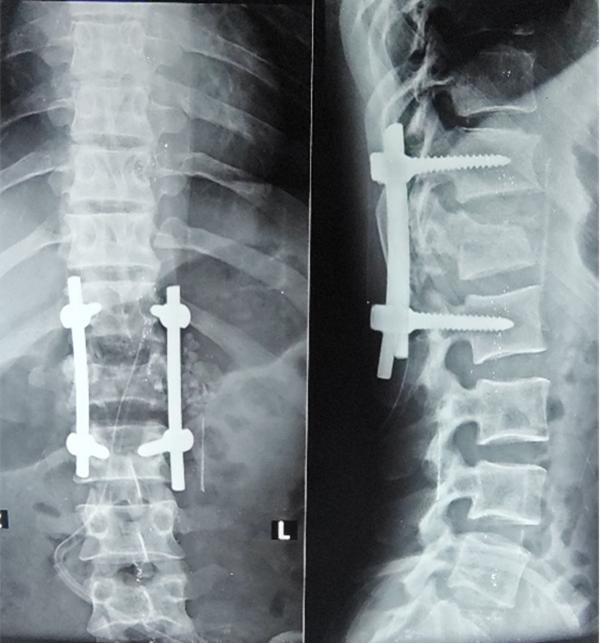

“切开,剥离,定位,置钉,减压”,手术过程就像术前预想的那样,术中发现腰1脊髓背侧硬膜囊与黄韧带粘连非常严重,小心翼翼的分离,牵开脊髓,敲击突出骨块,所幸过程相对比较顺利。但因为是脊柱陈旧性骨折,伤椎高度未能完美恢复,但最重要的减压固定已完成。阿明院长在旁边一直关注着手术的进程,当看到最后一次透视后,他放松的表情,满意的对两位中国医生竖起了大拇指。顺利完成术后,脱掉厚厚的铅衣后,周围人才发现两位医生的洗手衣都已被汗水浸透。

术后第三天,两位中国医生去病房探视病人,因术中无法采集正位,术后片略有瑕疵,但患者自诉双下肢力量较术前已经有所改善,这已经是神经损伤开始恢复的标志。骨折减压复位固定,也只是患者在康复的万里长征路上迈出了第一步,后面还有很漫长的康复过程。我们也衷心期待患者在中国医生的帮助下患者能早日康复,期待回头他能走着回来复诊。